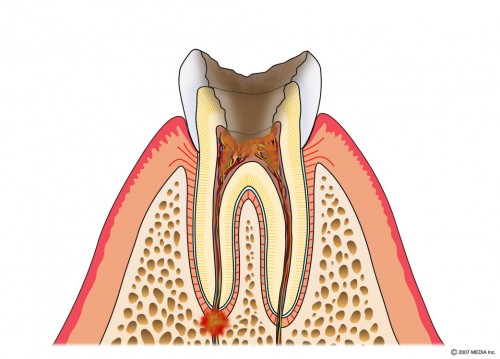

歯髄に達するむし歯

歯の神経を取ります→土台を立てます→被せものをつくります。

C3:歯髄に達するむし歯

むし歯が神経に達しています。

むし歯を取り神経の管に穴を開けます。

神経の冠を拡げていきます。

神経の管を拡げ終えたら→最終的な薬を詰めます。

土台の型どりをします→土台を付けます。

土台の周りを削ります→型どりをします

被せものが出来上がります。